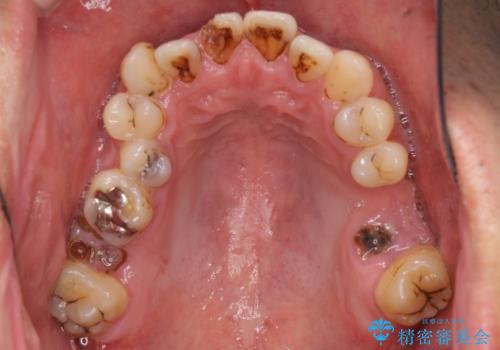

- 前歯や奥歯の虫歯を放置しており、それらの治療を契機に真っ白な歯にしたいとのことで来院された患者様です。

咬み合わせを改善するに当たって、抜歯しなければならない歯や歯列の改善が必要な箇所があったため、矯正治療やインプラント治療から始めていくこととしました。

不自然なくらい真っ白にしたいとのことでしたので、透明感のないフルジルコニアクラウンを用いて補綴することとしました。